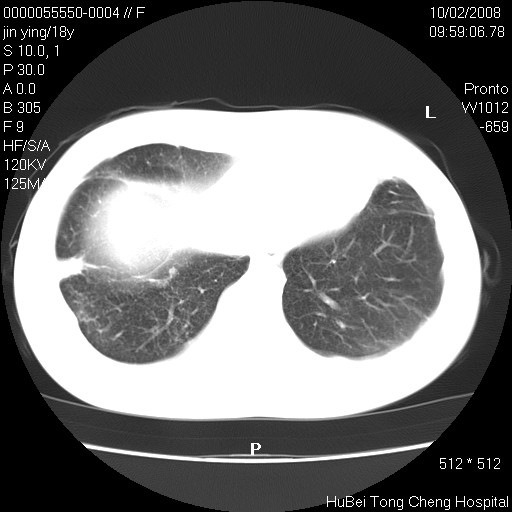

患者 女,18y。发热十余天,伴咳嗽。pe:t39⒈℃,bp 110/80mmhg,p 86次/min。神清,精神欠佳。双肺可闻及少许湿罗音。既往史不详。

临床诊断:肺部感染?

胸部ct轴位平扫(层厚10mm,螺距1.5,重建间隔10mm),图像如下: